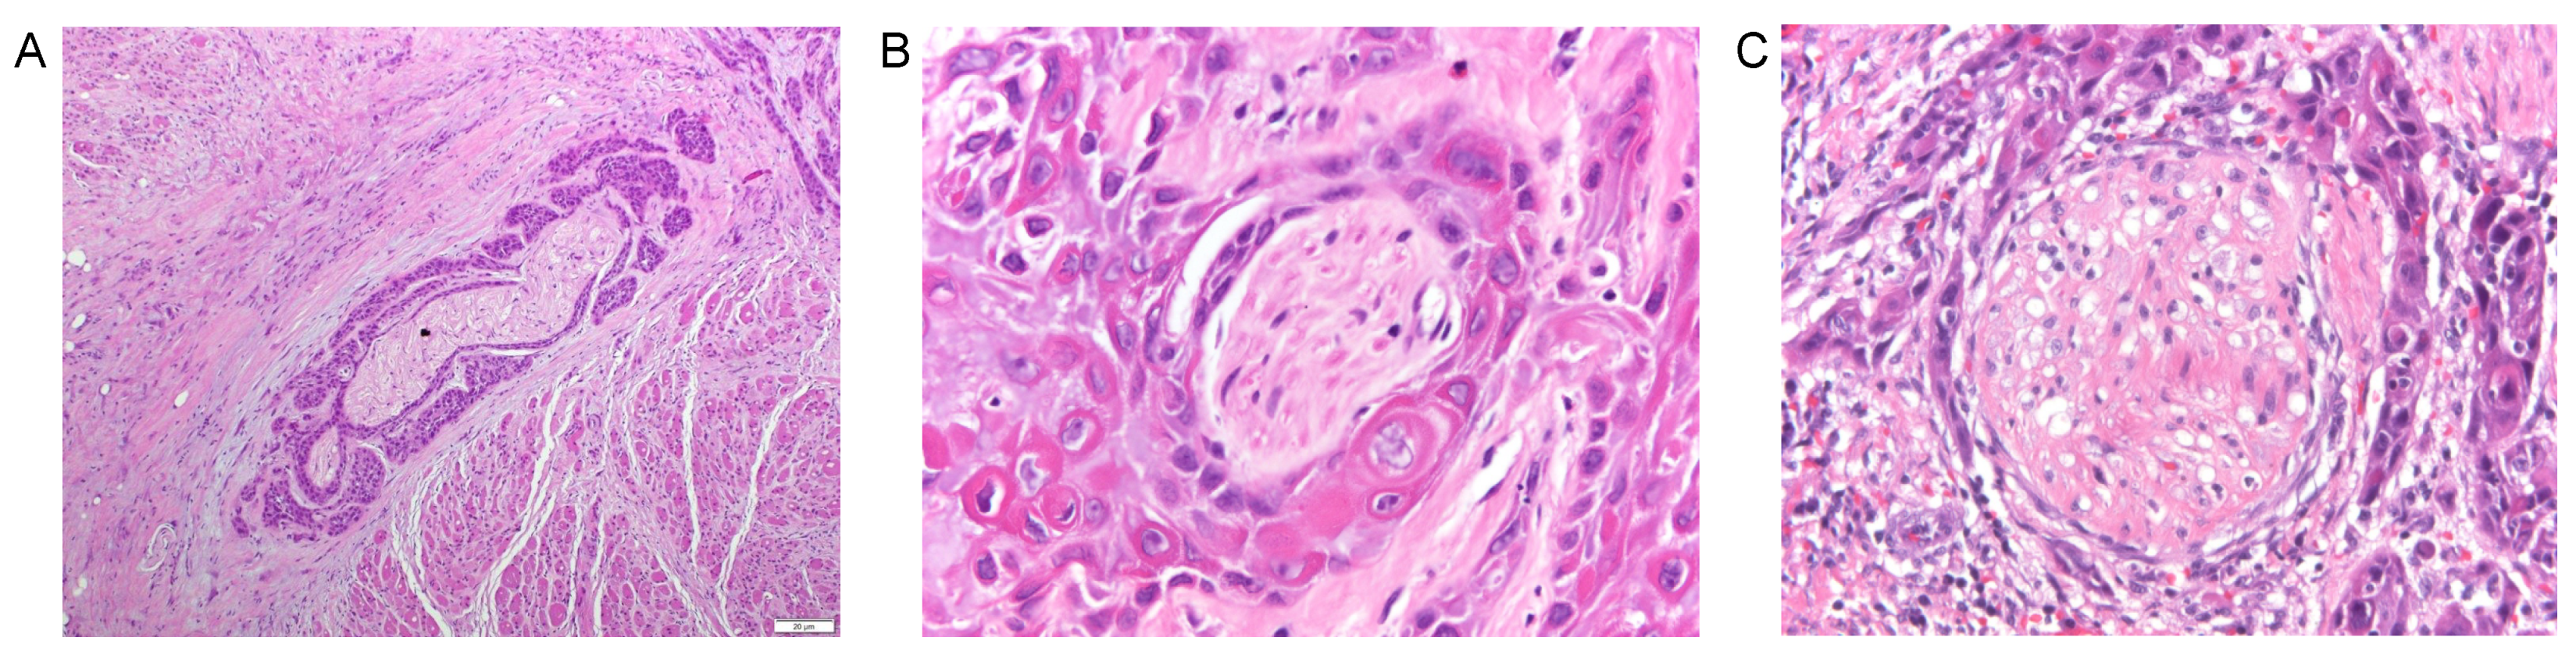

3. Definitions for Perineural Invasion (PNI)

5.1. Cellular Observations in Perineural Invasion